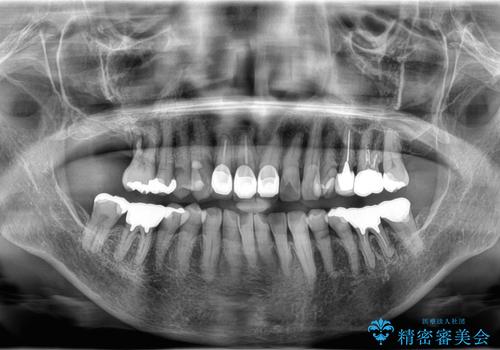

- 右上の奥歯(6番)が重度の歯周病により保存困難な状態であること、およびその後ろの7番もすでに失われていることを主訴にご来院されました。このままでは咬み合わせの機能が大きく低下してしまうため、抜歯後の早期回復と長期安定性を考慮し、インプラント治療を提案しました。治療計画は、

6番を抜歯すると同時にインプラントを埋入する抜歯即時埋入

失われた7番の部分にも同時にインプラントを埋入 の2本同時のインプラント埋入により、治療期間を短縮し、奥歯全体の機能再建を目指しました。

今回の治療では、まず重度歯周病の右上6番を慎重に抜歯し、その直後に6番と、すでに欠損していた7番の部分に、合わせて2本のインプラントを埋入しました。

抜歯即時埋入(6番): 抜歯と同時にインプラントを埋入することで、骨の吸収を最小限に抑え、治療期間を大幅に短縮しました。

7番のインプラント埋入: 6番と同時に埋入することで、治癒期間を一括で管理でき、効率的に治療を進めることができました。